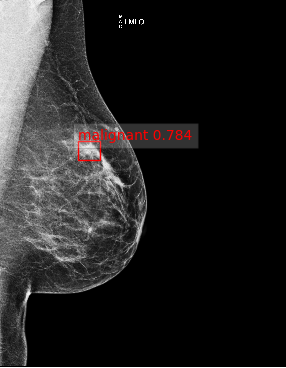

Based on these results, we submitted our final architecture described in Section 2 for testing on the large GH-Validation dataset. In the first sub-challenge, which records the AUC by breast purely on imaging and blinded to demographic information, we achieved AUC=0.879 (standard deviation: 0.00914), see Fig. 2(e), which is 0.005 above the top AUC in the competitive phase of the Challenge. It was also the highest single-model AUC in the collaborative phase, 0.014 below an ensemble of detection models, and higher than all patch-based models. The second sub-challenge is on subject-wise AUC, with access to both images and demographics. Despite ignoring demographics, our architecture gave AUC=0.868, behind only the top score in the competitive phase (a patch-based curriculum-trained model) by 0.006. Twenty-five method descriptions from this phase are available at synapse.org, but details of the collaborative phase, including performance of patch-based models trained on Optimam, is embargoed pending publication by the Challenge. Fig. 2 shows sample outputs from GH.

Refer to caption

Figure 2: (a) True positive prediction (p=0.90𝑝0.90p=0.90 probability of malignancy) of an inconspicuous lesion on a left MLO of a 73 year old woman. (b) True negative (malignancy: p=0.06𝑝0.06p=0.06) for left MLO view of a 66 year old woman. (c) False positive (p=0.78𝑝0.78p=0.78) on left MLO of a 43 year old woman, due to hyper-intense region. (d) False negative (p=0.03𝑝0.03p=0.03) for left CC view of a 61 year old woman. (e) ROC by breast, AUC = 0.879.